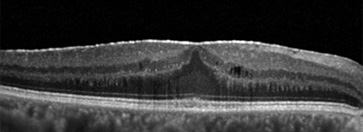

Gözde keskin ve renkli görmeyi sağlayan merkezi retina bölgesinin üzerinde parlak ve saydam zar şeklinde bir doku gelişmesine epiretinal membran adı verilir.